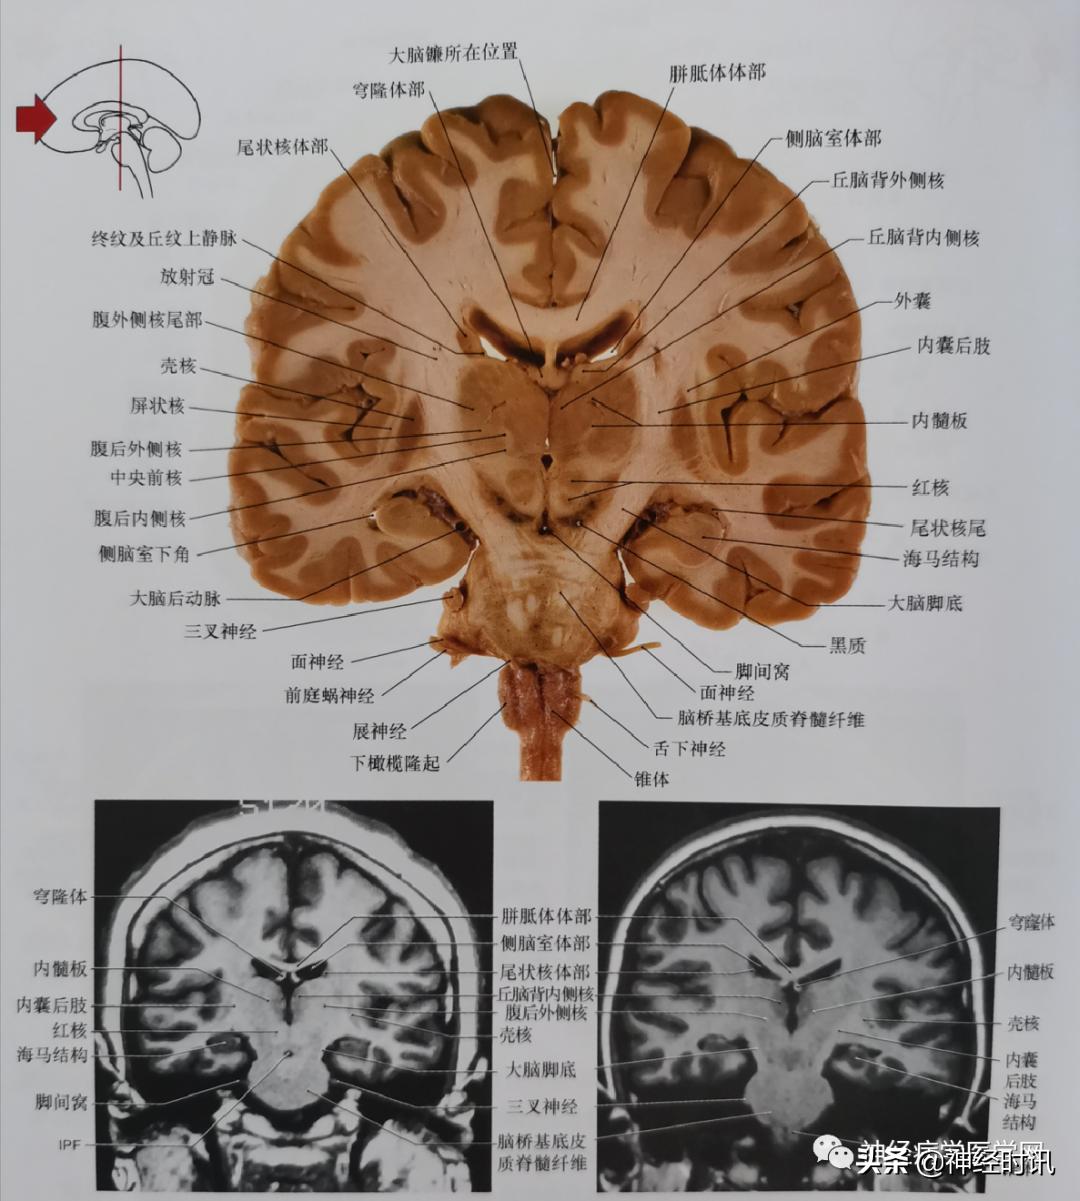

图5 通过丘脑腹外侧核尾部、中间块、丘脑腹后外侧核、红核、黑质、脑桥基底平面的冠状位影像。此平面儿完美地显示了内囊的纤维(切片中的内囊后肢)穿过大脑脚,进入桥基底(切片及磁共振影像可见);这些通过大脑脚的纤维,包括皮质脊髓纤维、皮质脑桥纤维(顶桥、枕桥、颞桥、额桥)及皮质核束纤维。

图6 通过丘脑枕核、内外侧膝状体核、中脑和脑桥被盖及延髓腹侧平面的冠状位影像。通过内囊后肢、大脑脚和桥基底皮质脊髓纤维正好定位于延髓的椎体部位。注意四叠体池的位置与第三脑室有显著的不同。在大脑切片与MRI影像均显示膝状体特征性地位于丘脑枕的下方。